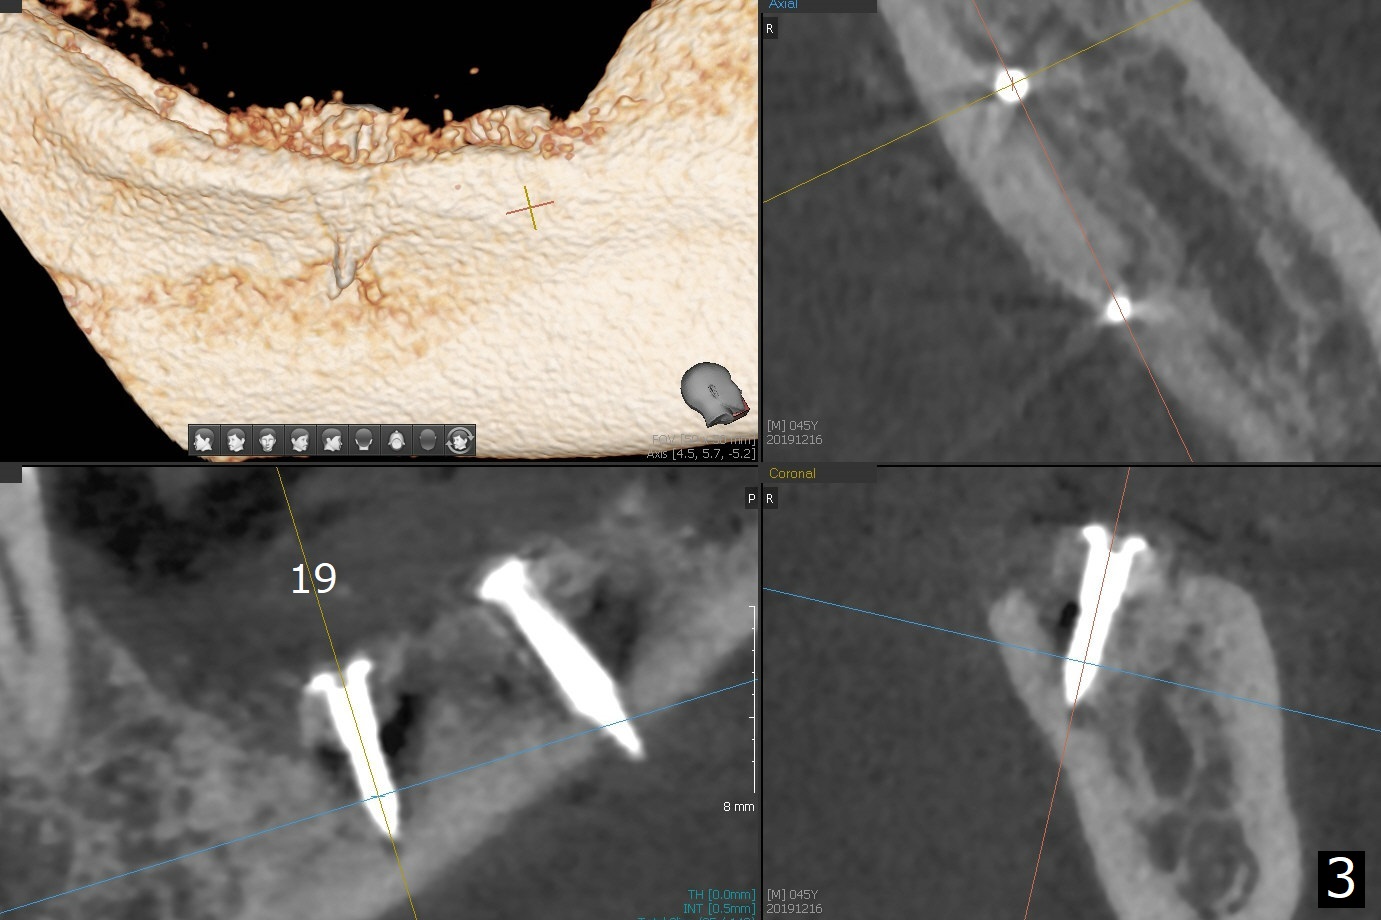

While the implant at #18 is easily removed, the one at #19 is superficial with buccal nonkeratinized gingiva (Fig.1). The latter is removed. Two small pieces of onlay graft is harvested from the left ramus and fixed in the defects with pins (Fig.2), surrounded by allograft with PRF. Since the pin at #18 looks violating the Inferior Alveolar Canal (Fig.2 C), CT is taken. In fact the pin perforates the lingual plate at #18 (Fig.4, as compared to Fig.3 (#19)). It leaves in place. Postop the wound dehisces with loss of allograft and exposure of the screws. The wound heals gradually mesiodistal with exposure of #18 screw 2.5 months postop. Follow up is disrupted by coronavirus pandemic.